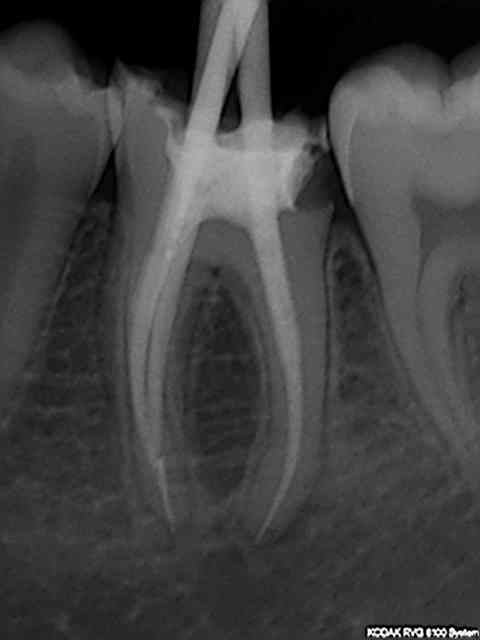

Bon allez, je le kiffe.

Et la pâte dans le dentaire inf c'est pas de moi.